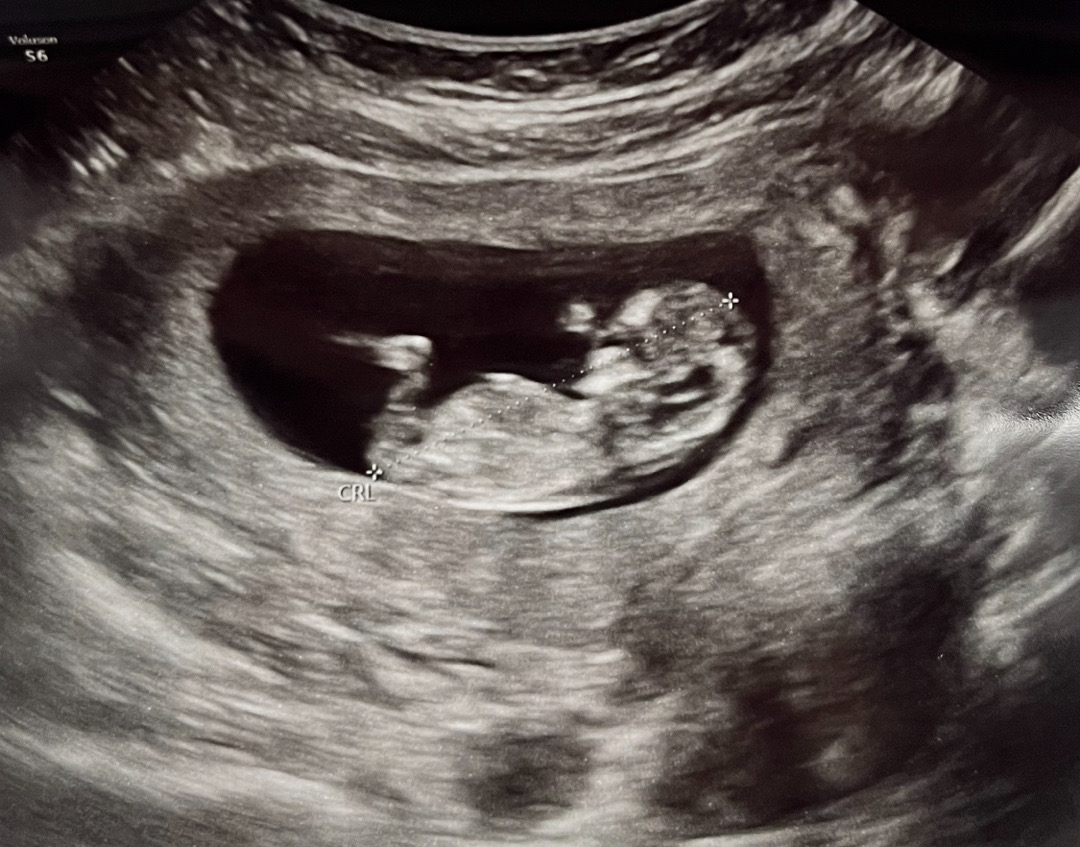

각도법 고수님들 봐주세용☺️

각도법 고수님들 어때 보이시나용?ㅎㅎ

아들같아요